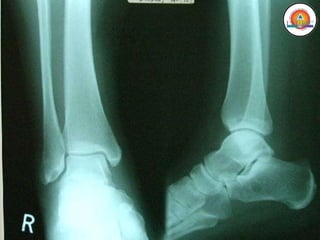

MIEMBRO INFERIOR

• Cintura pélvica

• Cadera

• Muslo (Fémur)

• Rodilla

• Pierna (Tibia y Peroné)

• Tobillo

• Pie (Tarso, Metatarso y Falanges)

Huesos:

• Pelvis

• Fémur

• Rótula

• Tibia

• Peroné

• Tarso

• Metatarso

• Falanges

Pelvis

Fémur (y rótula)

Tibia y Peroné

Pie